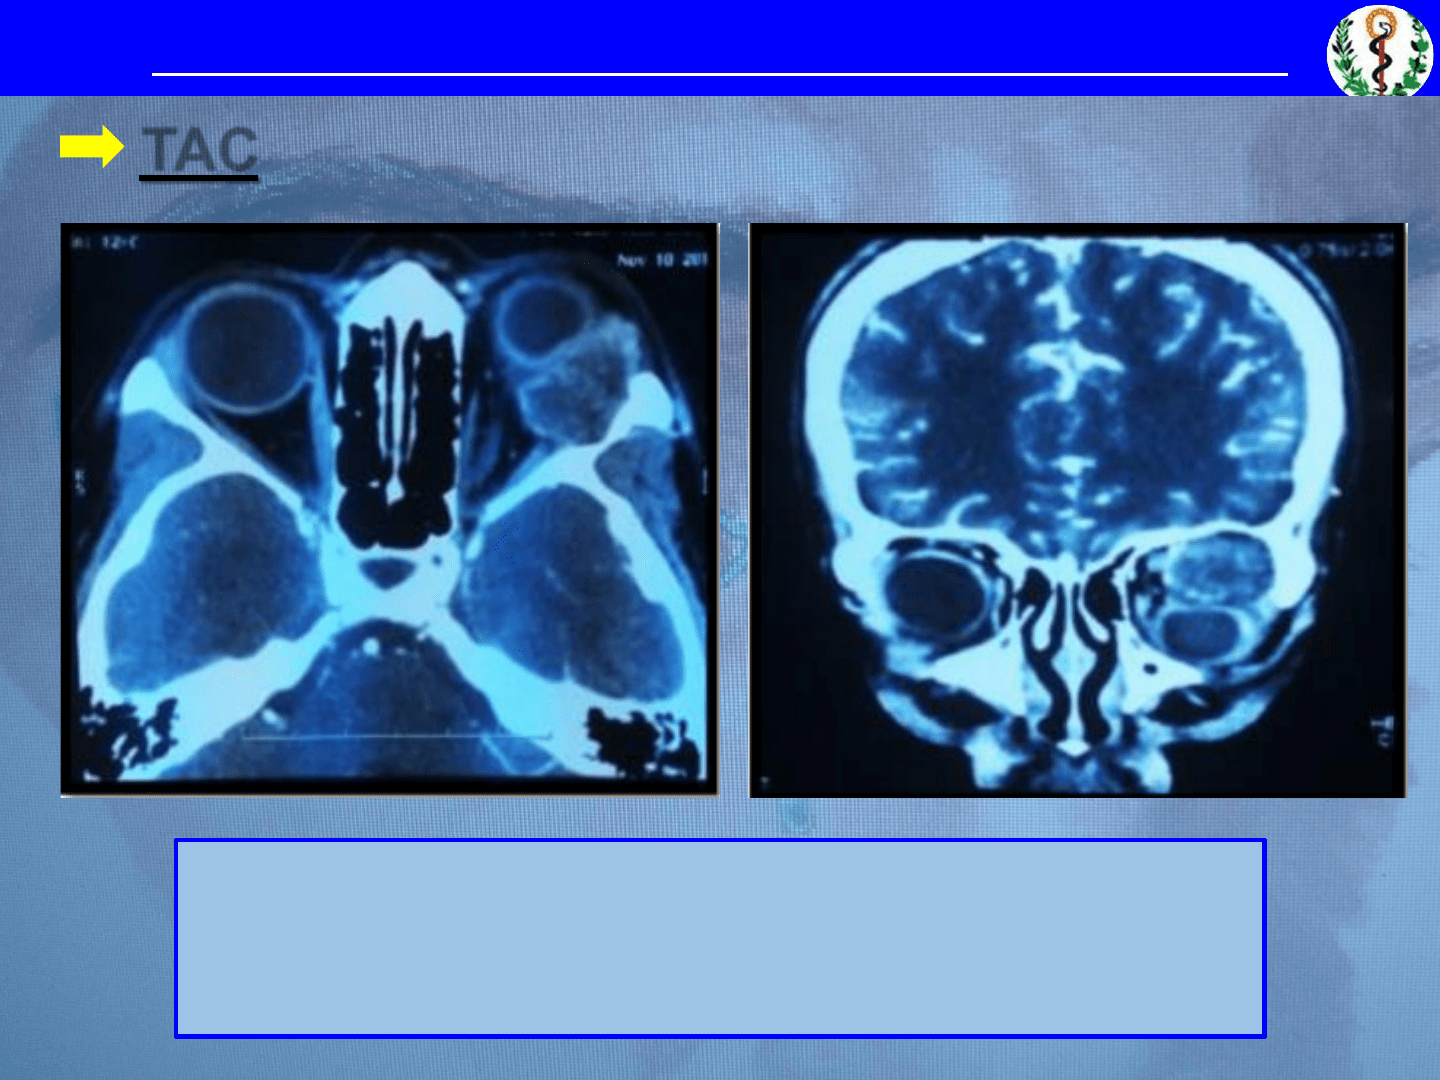

o Afecta predominantemente el

lóbulo orbitario de la GL

o Exoftalmo de moderado a severo

(desviación inferonasal del GO)